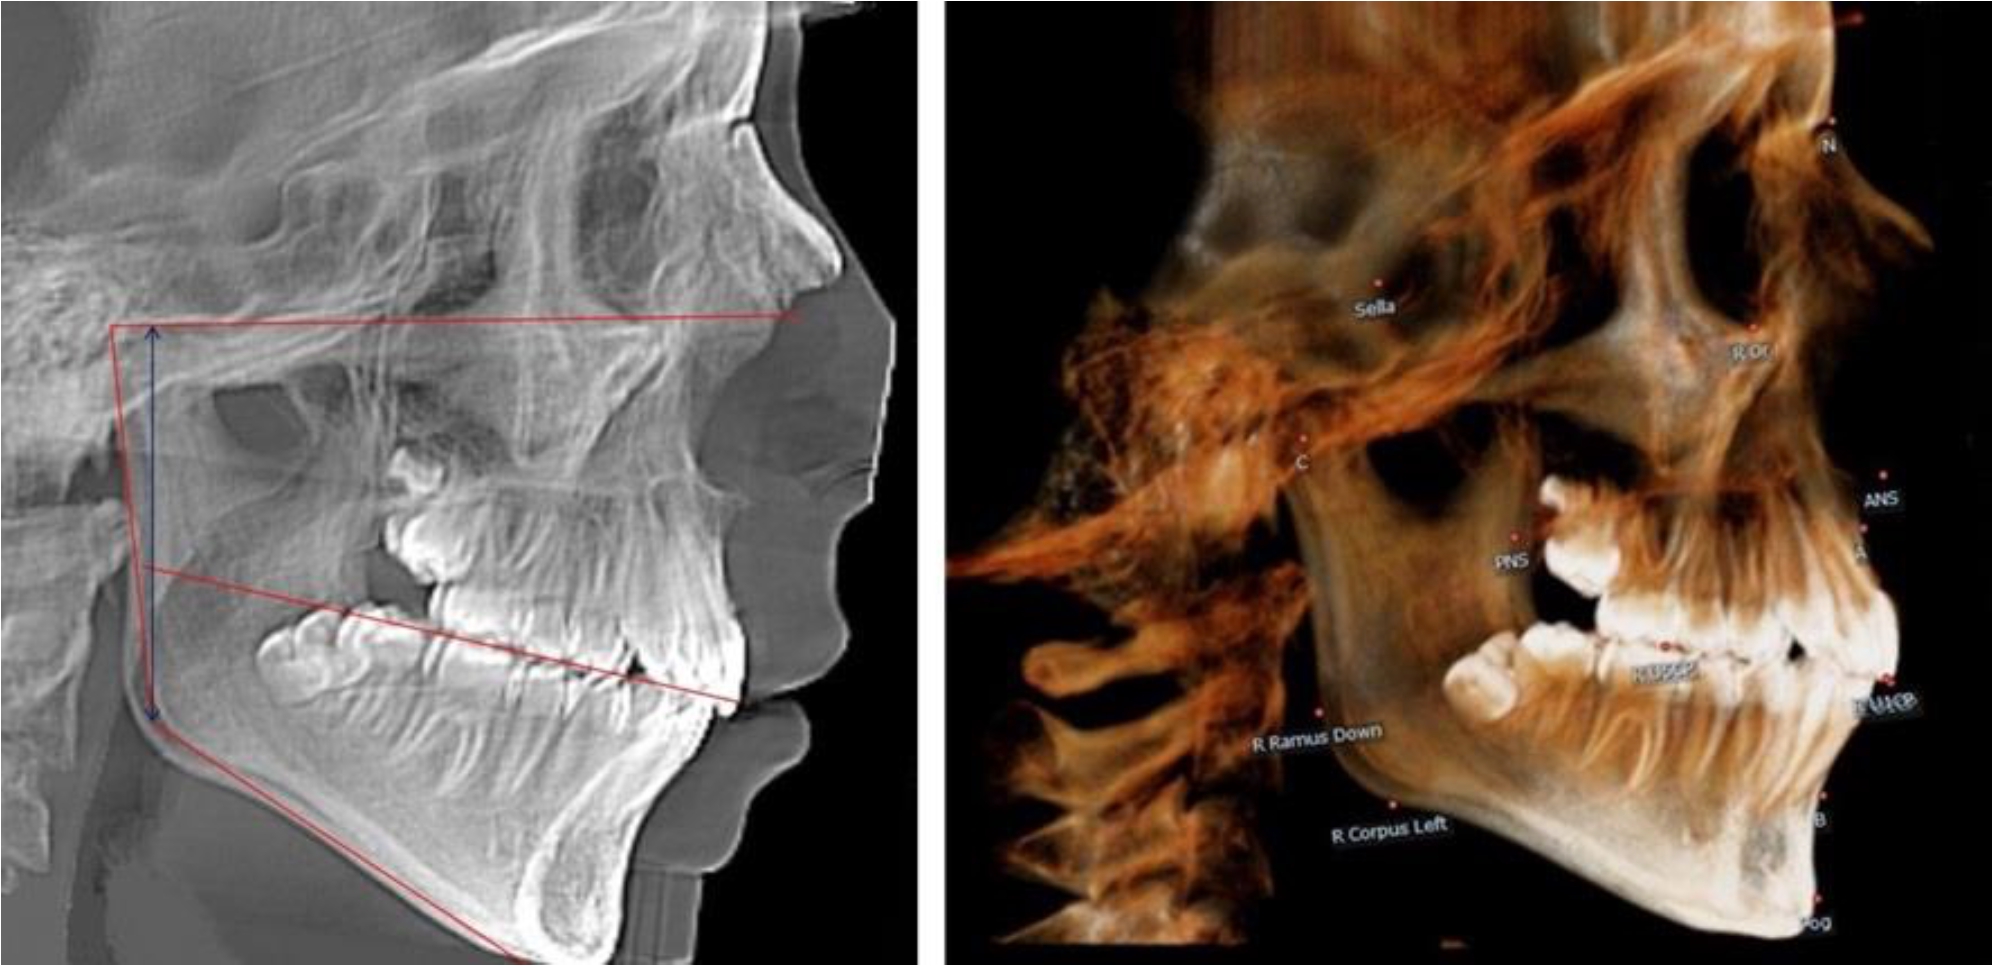

На всех парах рентгенограмм угол нижней челюсти, измеренный на телерентгенограмме, так же, как и в 1-й группе, соответствовал углу, полученному при построении угла на ортопантомограмме. Окклюзионная линия делила ветвь на два отдела (рис. 2).

Рис. 2. ТРГ и ОПТГ пациента после прорезывания первых постоянных моляров

Как на ортопантомограмме, так и на телерентгенограмме высота ветви у детей 2-й группы составляла (46,54 ± 2,87) мм, что было несколько больше, чем у детей 1-й группы (р ˂ 0,05). При этом высота верхней окклюзионно-суставной части была (25,42 ± 1,59) мм, а нижней – (21,12 ± 1,77) мм.

Таким образом, верхняя часть была несколько больше нижней, что и определяло рост обеих частей ветви.

Относительные показатели соразмерности частей ветви нижней челюсти показали, что отношение высоты верхней части ветви к нижней в среднем составляло 1,21 ± 0,12. Отношение общей высоты ветви к верхней ее части составляло 1,83 ± 0,13, а отношение общей высоты ветви к нижней ее части было 2,20 ± 0,16, и достоверных различий по относительному показателю отношения всей высоты к верхней и нижней челюсти нами не отмечено (р ˃ 0,05).